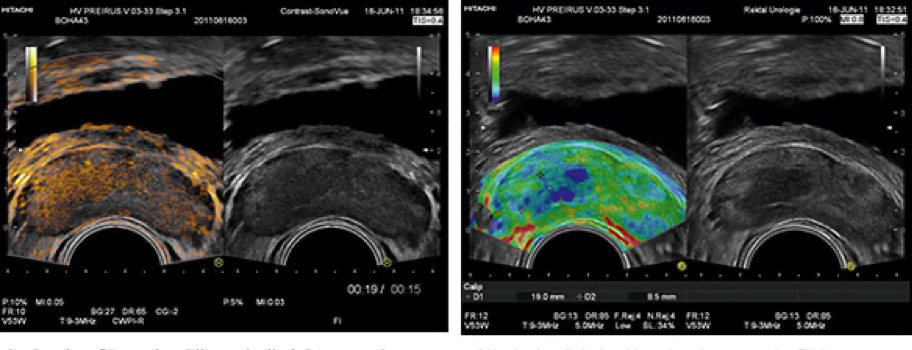

Ultraschalldiagnostik mit Duplexsonographie und Elastographie

Messung der Elastizität des Prostatagewebes

Die Elastographie der Prostata ist ein bildgebende Verfahren zur verbesserten Diagnostik des Prostatakarzinoms. Sie wird im Rahmen der Ultraschalluntersuchung routinemäßig durchgeführt, so dass hier eine große Erfahrung mit der Methode besteht.

Die Untersuchung ist einfach und unterscheidet sich für Sie nicht vom herkömmlichen transrektalen Ultraschall der Prostata, da die Technik im verwendeten System integriert ist.

Karzinomgewebe ist deutlich härter als normales Prostatagewebe. Die Elastographie misst die Härte des Prostatagewebes und macht diese auf dem Untersuchungsmonitor farblich sichtbar. Die verhärteten Areale (im Ultraschallbild blau dargestellt) können einen wichtigen Hinweis auf ein mögliches Krankheitsgeschehen geben.

Da aber auch Verkalkungen und narbiges Gewebe bei chronischen Entzündungen härter als Normalgewebe sind, kann die Methode hier nicht vom Karzinom unterscheiden.

Die Elastographie ist damit keine absolut sichere diagnostische Maßnahme, dient aber als wertvoller Baustein in der Prostatakarzinomdiagnostik und kann insbesondere auch zur gezielten Zusatzbiopsie bei der Entnahme von Gewebsproben zum Karzinomausschluss herangezogen werden.